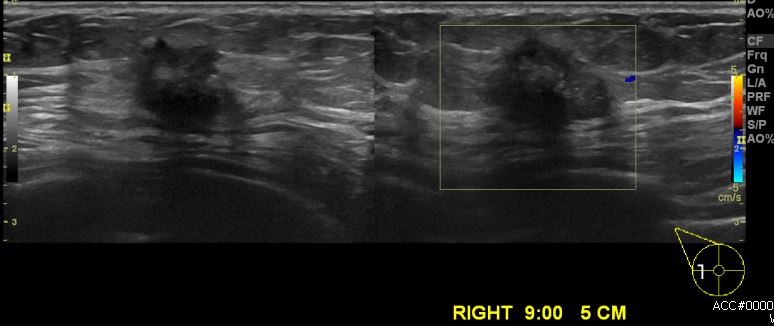

우측 유방에 만져지는 멍울로 내원하신 60대 여성 분으로  우측 9시 방향에서 5cm 거리의 만져지는 혹 중심핵생검 시행하여 우측 침윤성 유관암 진단 되었습니다.